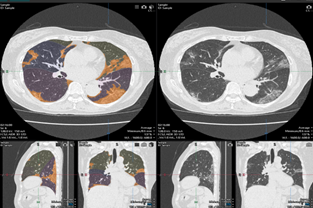

COVID-19肺炎解析ソフトウェア画面例

(2) COVID-19肺炎像判定機能が注目した肺野内の領域を表示します。